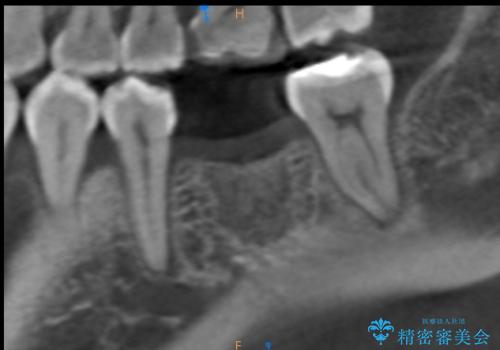

その過程で左下の6番目の歯は治療が必要な状態であることが分かり、被せ物を外して内部を確認してみると根が破折してしまっていることが判明しました。

歯が深い位置で破折している場合は基本的には抜歯が選択されます。

様々な治療プランを患者さんと相談させて頂き、最終的にインプラントで噛み合わせを回復させていくこととなり、まず悪くなっている歯を抜歯することから開始しました。